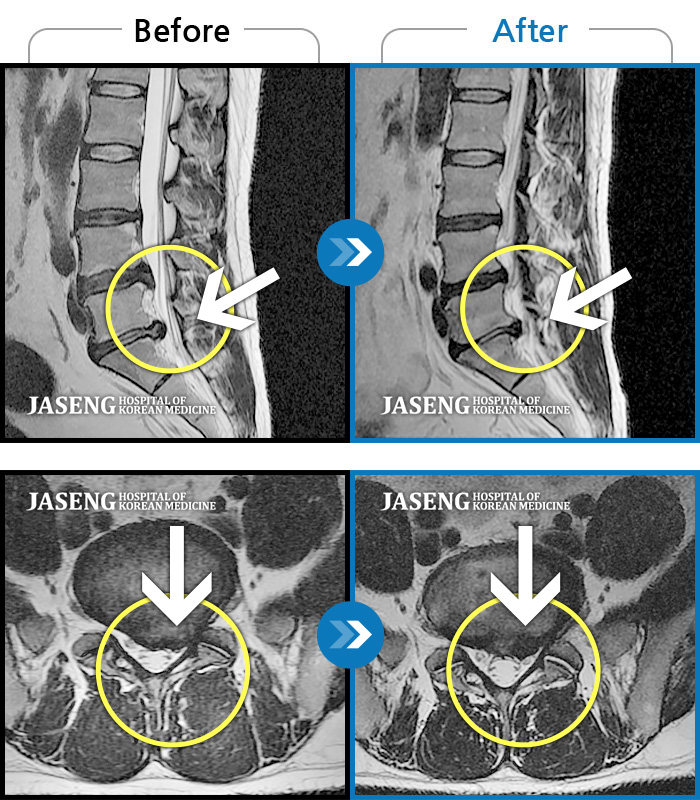

허리디스크

일산 · 김태용 원장

허리와 우측다리가 심하게 저렸다.

촬영시기

2020.05.07 ~ 2020.12.29

2021.02.26